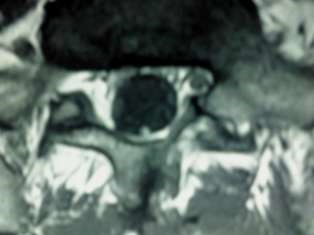

Spinal Tumors

A spinal tumor is a growth that develops within your spinal canal or within the bones of your spine. A spinal cord tumor, also called an intradural tumor, is a spinal tumor that that begins within the spinal cord or the covering.